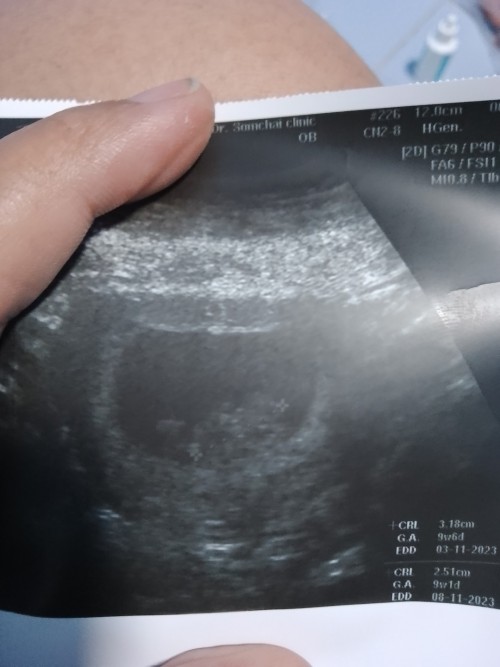

ตัวจิ๋ว9wแล้วว🎉

มีแม่ๆบ้านไหนซาวด์ตอน9วีคแล้วเห็นตัวเท่านี้บ้างไหมคะ หรือ มีแขนขา ครบกว่านี้ แต่บ้านนี้เพิ่งมีแขนจิ๋วๆออกมา ตื่นเต้นมากตอนเห็นหัวใจน้อง มันดีใจไปหมดเลย🥹👶🏻🤍

ของเราตอน 9w+1 ตอนเห็นหัวใจเจ้าจิ๋วเต้นแทบร้องไห้เลย ตอนนี้ 10w+1แล้วจ้า

ของเราในเครื่องซาว8w3d ตัวจิ๋วมากเลยค่ะ